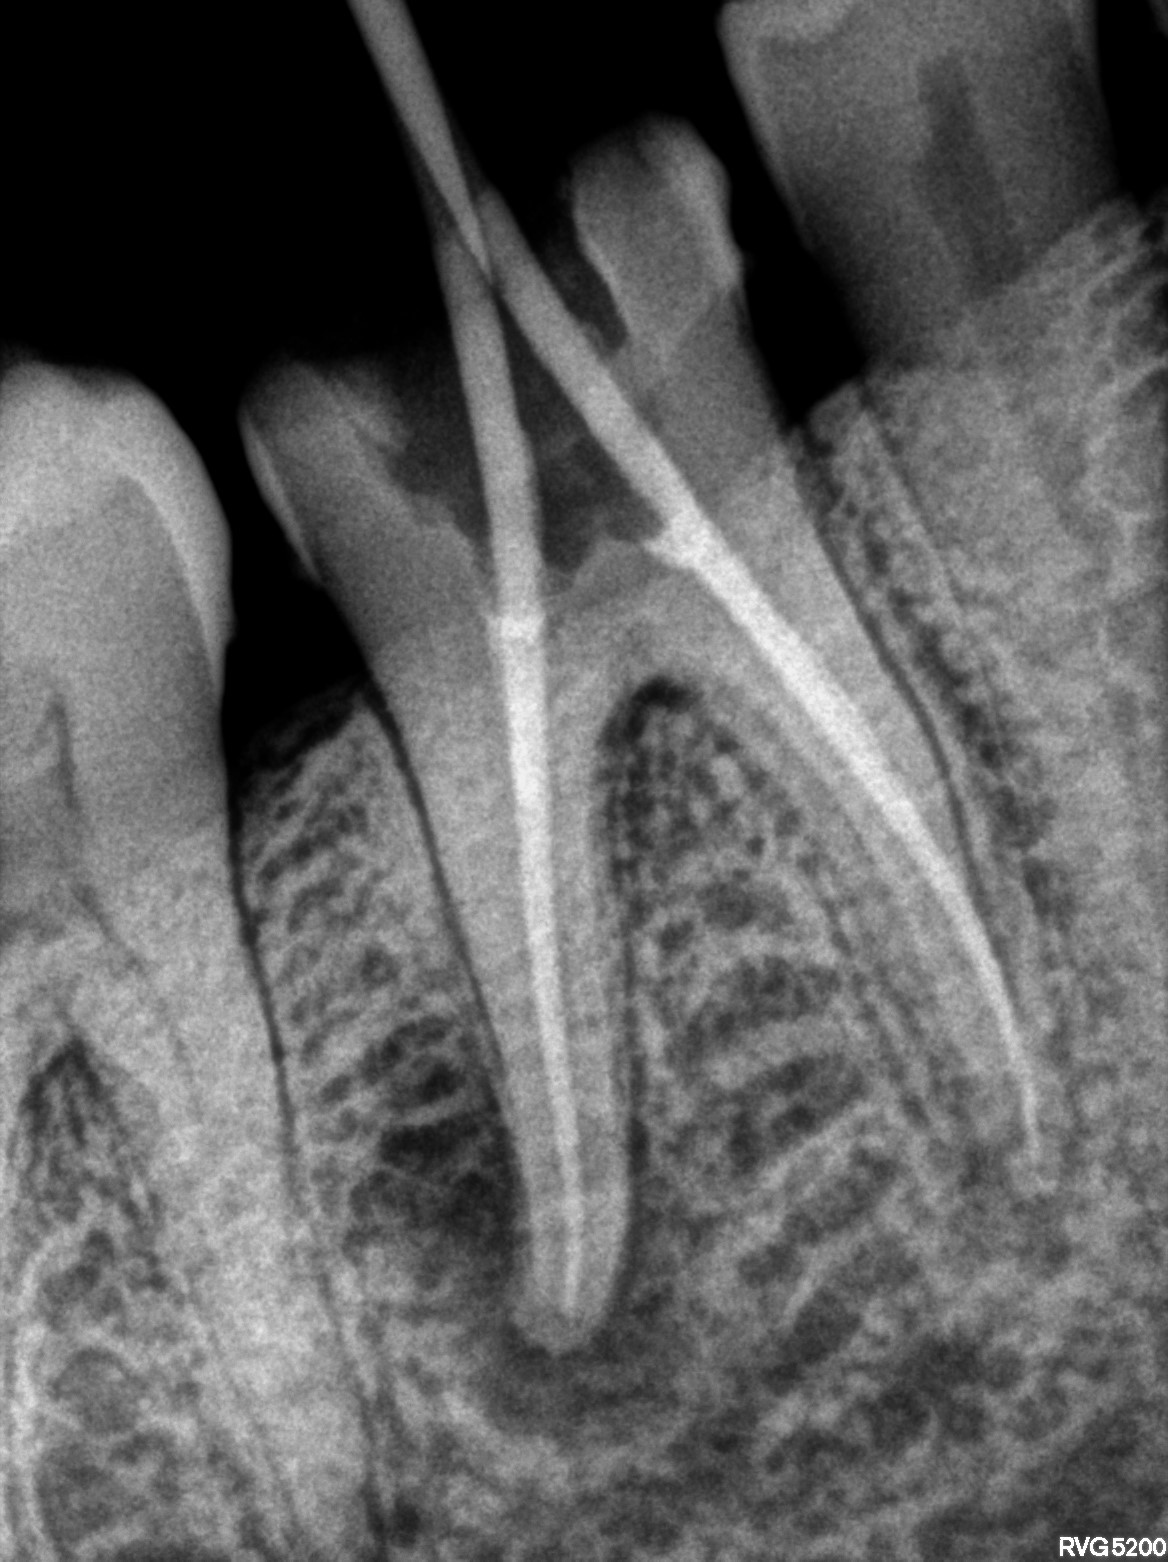

Dental Radiographs FHIR: DocumentReference · LOINC 24641-7

xray_1769185475_0.jpg

24641-7